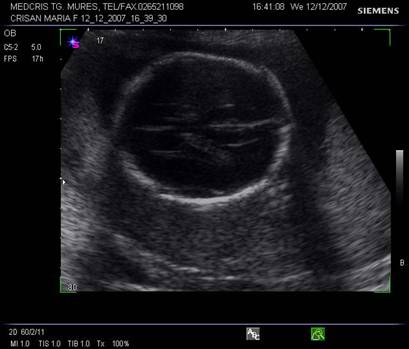

Linia de mijloc hiperecogena frontoocipitala este formata anterior si posterior de falx cerebri si fisura interemisferica, central de septum pellucidum. La sfarsitul primului trimestru de sarcina, linia de mijloc hiperecogena este flancata la distanta de o pereche de ventriculi laterali, ce inconjoara plexurile choroide ecogene. Din saptamana a 15-a cresterea cortexului devine vizibila, la marginea ventriculilor laterali, ca o margine hipoecogena. Partea posterioara a ventriculilor laterali ramane ocupata de plexurile choroide, in timp ce coarnele anterioare contin doar fluid. Dupa saptamana 19-a ventriculii laterali au caractere constante pe tot parcursul sarcinii.[1,3,8,13,14]

Planul

II demonstreaza ventriculii laterali hipoecogeni si parte din plexurile

choroide ecogene.

Fig. nr. 150. Planul II de sectiune transversala a craniului fetal.